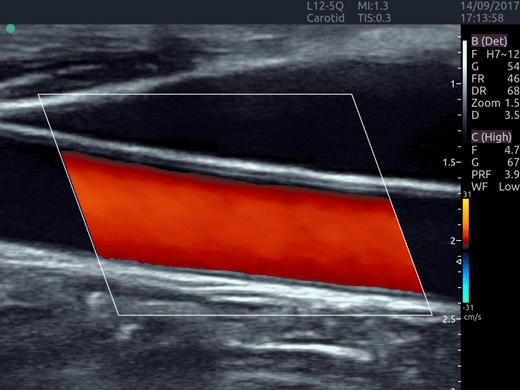

Invictus E5

O ultrassom Invictus E5 apresenta um design moderno e exclusivo, com perfeito fluxo de trabalho e interface intuitiva.

Dentre suas características inovadoras, podemos destacar a tela em LCD com rotação de 60° para ambos os lados, para otimização da visualização durante os exames; tela touch screen com menu totalmente customizável; painel de controle totalmente selado para facilitar limpeza e desinfecção da superfície, o que o torna referência para ser utilizado principalmente em Centro Cirúrgico.

Apresenta excelente qualidade de imagem, trabalho otimizado através de presets pré-determinados, sensibilidade e eficiência em aplicações de Point of Care e portanto, uma perfeita relação custo benefício.